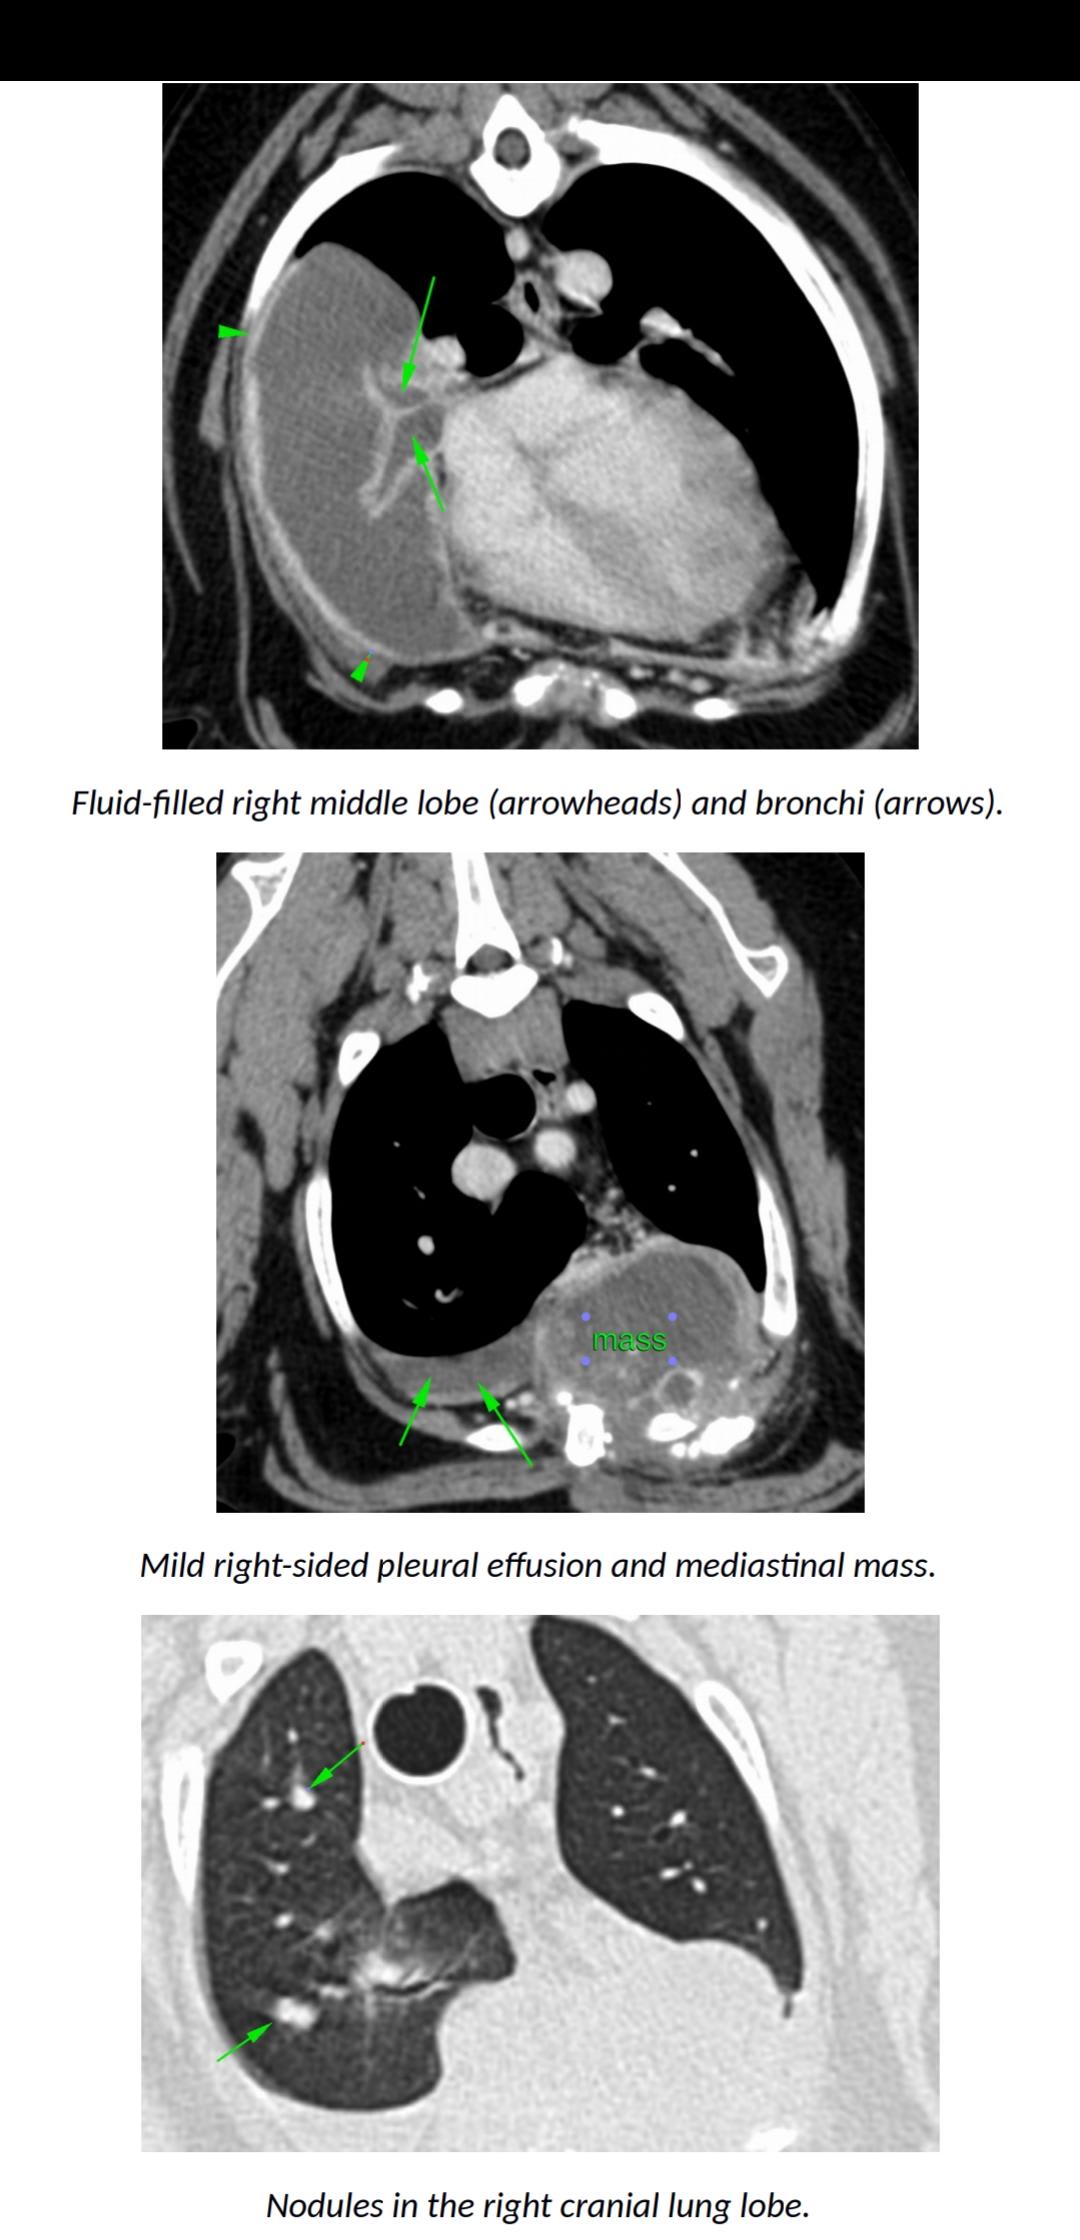

Hello. Yogi was out through many procedures in March/April. The tissue biospsys were not conclusive but likely cancer was the outcome and that he would go downhill quickly and to bring him back for pain medication when he did. It is November now and he is as normal as a year ago. Walking, running, eating well and no pain. Is this normal or could the diagnosis be something completely different. He is getting new lumps on his body but seems very comfortable. An experienced opinion will be great

Thanks for using Petco Pet Education Center, formerly Petcoach! I would agree that the mediastinal mass is very evident and I would also be very suspicious that it is in fact cancer even if the biopsy did not show that. Sometimes dogs appear to be comfortable even when they are in pain. These new lumps you describe could be somewhat related to this or may be unrelated. I think it would be ideal to have Yogi reevaluated to see if the mass has progressed and if the nodules in the lungs (which likely represent spread of the tumor) have also progressed. I would maintain him on pain control medications even if he does not appear to be obviously in pain. Good luck and have a great day!